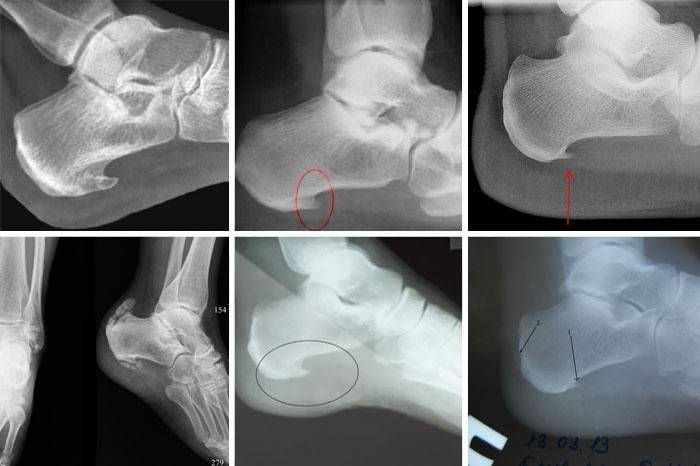

Diagnoza choroby

Zapalenie powięzi podeszwy (kod ICD-10: M77.3) jest chorobą charakteryzującą się stanem zapalnym tkanek miękkich w okolicy pięty, który prowadzi do proliferacji kości w obszarze podeszwy. Na zewnątrz formacja jest podobna do kołka lub kolca, ale tylko lekarz może ustalić dokładną diagnozę. Jej objawy:

- Rentgen stopy. Rentgen z maksymalną dokładnością pokaże, czy istnieje formacja, kolec, który powoduje ból. Jest to niezawodna metoda badania lekarskiego, za pomocą której można potwierdzić diagnozę.

Chirurgia

Istnieje kilka rodzajów operacji:

- Klasyczna operacja otwarta. Ta opcja jest skuteczna, ale jednocześnie duży obszar obrażeń, a okres rekonwalescencji trwa około 2 miesięcy.

- Endoskopowe leczenie chirurgiczne - podczas operacji lekarz wykonuje jedno wycięcie z dna boków pięty: do jednego wkłada się kamerę, aby kontrolować zabieg, a instrument chirurgiczny do drugiego. Endoskopia jest popularna, ponieważ nie jest bardzo traumatyczna, proces odzyskiwania jest szybki i bez komplikacji.

- Minimalnie inwazyjne rozwarstwienie powięzi. Po niewielkim nacięciu pięty lekarz wkłada do niej mikrokalpel i odcina wzrost. Następnie stosuje się rurkę z młynem, który miele kość. Zalety metody: szybki powrót do zdrowia po operacji. Wady: niemożność lekarza, aby zobaczyć, jak przebiega proces operacji, co dzieje się pod skórą; sprzęt do tego rodzaju operacji znajduje się w kilku klinikach.